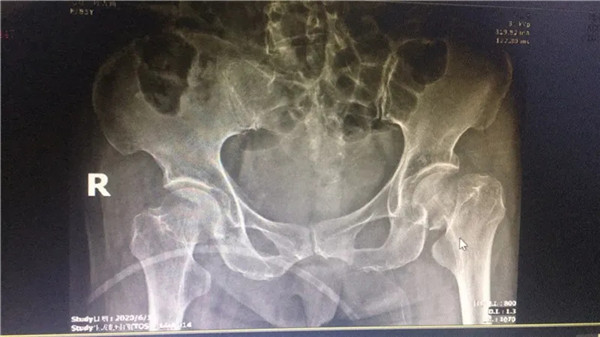

術(shù)前

經(jīng)拍片顯示,陳阿婆左側(cè)股骨頸骨折,須入院手術(shù)治療。一聽要手術(shù),家人便不禁擔(dān)憂起來(lái),這么大年紀(jì)動(dòng)手術(shù),身體吃得消嗎?危立軍副院長(zhǎng)解釋道:高齡病人股骨頸骨折臥床,會(huì)導(dǎo)致一系列嚴(yán)重的并發(fā)癥,如疼痛,肺炎、血栓、泌尿系感染等等。隨便哪一項(xiàng)發(fā)生,對(duì)病人都是致命打擊,如果病人身體情況不是很差,還是建議進(jìn)行手術(shù),人工關(guān)節(jié)置換,能讓病人盡早恢復(fù)患肢活動(dòng),縮短臥床時(shí)間,降低死亡率及其他并發(fā)癥的發(fā)生幾率。在聽了危副院長(zhǎng)的介紹后,家人遂即辦理了住院手續(xù)。